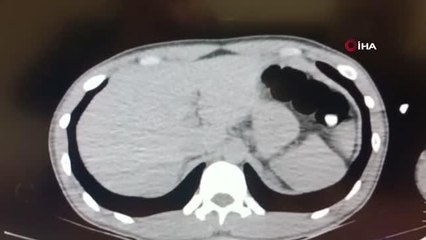

- Denizli Emniyet Müdürlüğünden görüntü - Zanlının adliyeye sevkinden görüntüMidesinde uyuşturucu taşıyan İranlı yakalandı - Denizli 'de, paketler halinde yutarak ülkesinden uyuşturucu getirdiği belirlenen zanlı tutuklandıDENİZLİ (AA) - Küçük paketler halindeki uyuşturucuyu yutarak ülkesinden Denizli 'ye getiren İran uyruklu zanlı yakalandı.İl Emniyet Müdürlüğü Narkotik Suçlarla Mücadele Şubesi ekipleri, yurt dışından bazı kişilerin küçük gramajlarla paketledikleri uyuşturucuyu yutarak Türkiye'ye getirdikleri bilgisi üzerine çalışma başlattı.İran uyruklu H.H'nin, bu yöntemle ülkesinden Denizli 'ye uyuşturucu getirdiği ihbarı üzerine harekete geçen ekipler, zanlıyı kent merkezinde yakaladı. Denizli Devlet Hastanesine sevk edilen şüphelinin mide ve bağırsaklarında 16 paket halinde uyuşturucu bulunduğu belirlendi. Toplam 112 gramlık uyuşturucu paketleri, tıbbi müdahaleyle zanlının vücudundan çıkarıldı.İşlemlerin ardından adliyeye sevk edilen H.H, nöbetçi sulh ceza hakimliğince tutuklandı.